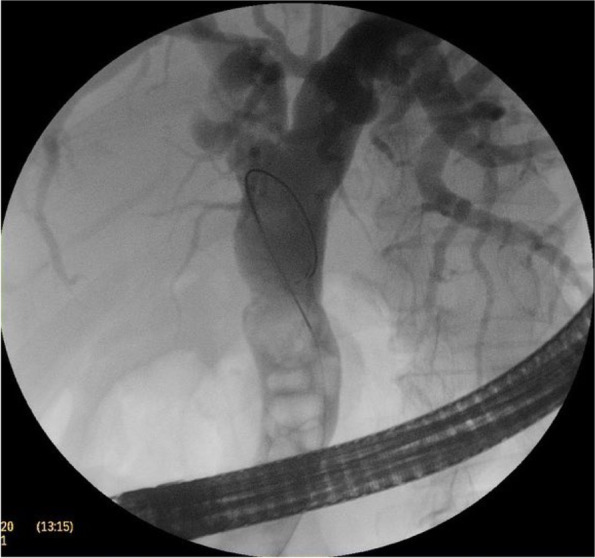

The CBD was cannulated after strenuous extraction of a long (20 cm) catheter that was largely displaced into the duodenal lumen. Cholangiogram revealed mildly dilated CBD with multiple large stones accompanied by mildly dilated central biliary radicals. Surprisingly, an old stent was hardly seen inside the dilated CBD, with mild dilatation of the intrahepatic biliary channels (Figs. 4, 5, and 6).

Papillotomy and papilloplasty were undertaken followed by stones’ extraction by a balloon extractor. The procedure was ended by inserting 2 plastic stents (10 cm× 10 f), and a flow of thick dark bile was inspected.